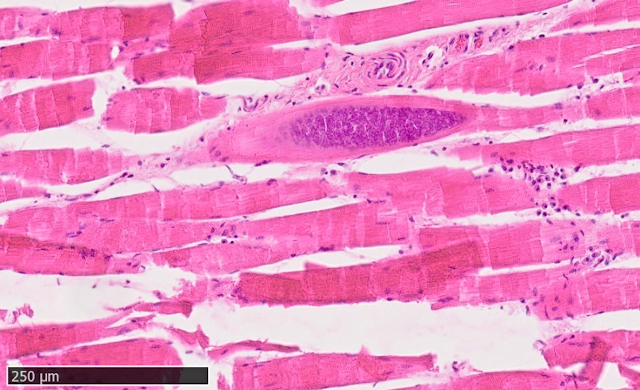

Die Muskelproben wurden kulturell auf bakterielle Infektionserreger untersucht, jedoch mit negativem Ergebnis. Parallel dazu wurden die Muskulatur feingeweblich (histologisch) untersucht. Das histologische Bild der Muskelfleischproben zeigte eine starke Einwanderung von Entzündungszellen in das Gewebe mit Zelluntergängen (Nekrose) und einem massiven Befall mit Sarkosporidienzysten in diesen Bereichen.

Abbildung 3: Reh. Histologische Untersuchung der Muskelfleischprobe: Nahansicht Skelettmuskulatur mit Entzündung und Sarkosporidienzysten (Pfeile)

Abbildung 4: Reh. Histologische Untersuchung der Muskelfleischprobe: Nahansicht Sarkosporidienzyste in der Skelettmuskulatur

In der Entzündungsreaktion lag ein hoher Anteil von spezialisierten weißen Blutkörperchen vor - den eosinophilen Granulozyten. Diese spielen als Teil des Immunsystems bei der Abwehr von Parasiten eine bedeutende Rolle. Das vorliegende Erkrankungsbild wurde als eosinophile Myositis verursacht durch Sarkosporidien diagnostiziert. Die Grünverfärbung der Muskulatur ist durch die enzymatische Zerstörung des Muskelgewebes durch die eosinophilen Granulozyten und die Bildung von biologischen Abbauprodukten zu erklären.